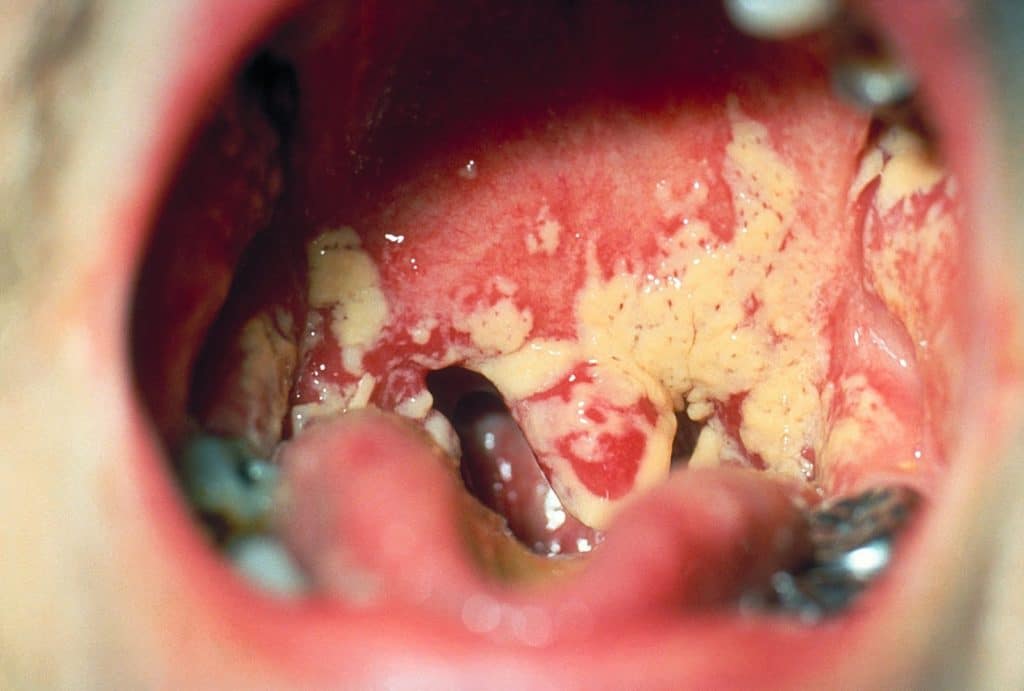

Грибок в горлі, особливості прояву якого можна побачити на фото з зображенням ураженої зони, провокується наступними причинами і факторами:

Зовні грибок на слизовій нагадує сирну масу

- Білі виділення на поверхні слизової оболонки, що нагадують за консистенцією сирну масу;

Головним симптомом того, що в горлі знаходяться патогенні грибки, є творожистие виділення і наліт. Вони поступово накопичуються і покривають собою окремі частини носоглотки. Білі крупинки добре видно на яскраво-червоній слизовій оболонці, яка збуджена.

На мигдалинах, мовою, задній стінці глотки утворюються мікотичні вогнища, що нагадують сирнистий наліт білого, жовтуватого або сіруватого кольору. Слизова оболонка у мигдалин пошкоджується і покривається тріщинами.